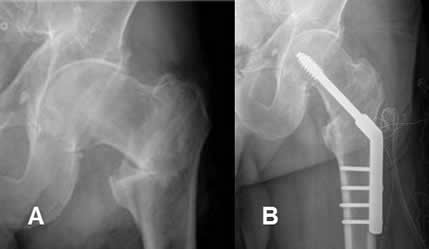

Fig 97. Tornillos de cortical.

A: Rx AP: Fractura conminuta del fémur distal.

B: Rx AP. Fractura fijada con placa de compresión y tornillos de cortical. El foco principal de la fractura está atravesado por 2 tornillos y los extremos de los tornillos penetran en la cortical contralateral.